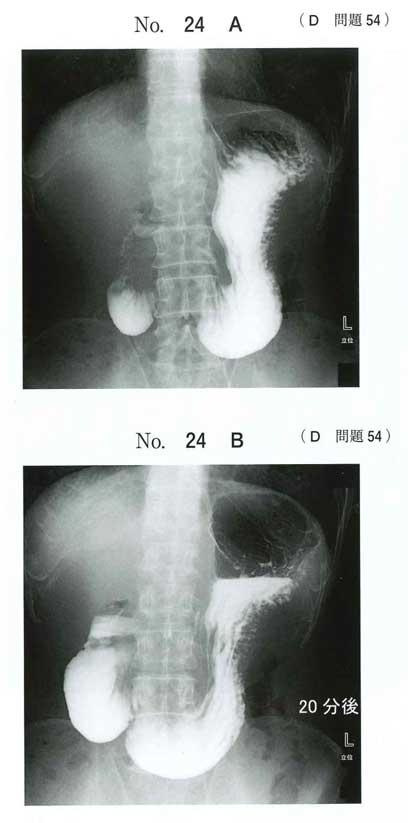

120D-54 120D-54AB

やせ型の人に多く,前屈の姿勢で軽快することが決め手かな